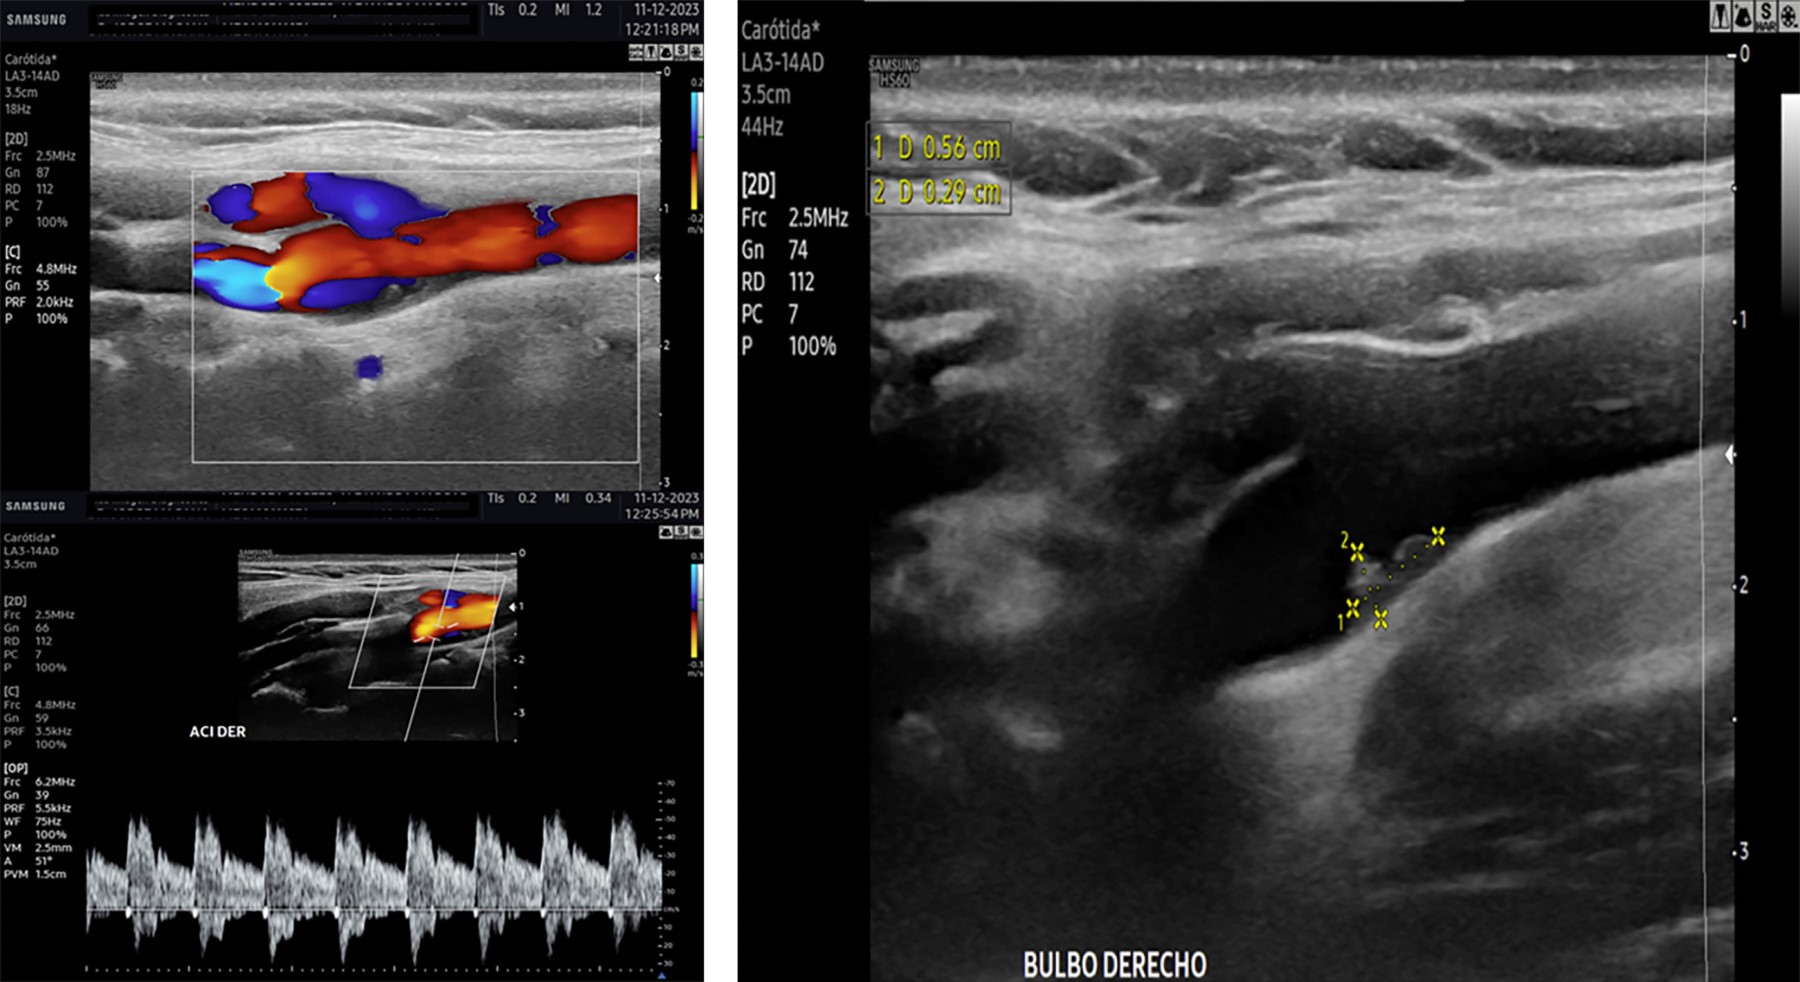

Femenino de 40 años con ataque isquémico transitorio (AIT), en la que se efectuó ultrasonido y angiotomografía que mostraron banda carotídea ipsilateral. La displasia fibromuscular atípica del bulbo o banda carotídea es una patología no ateromatosa implicada en la aparición de infartos cerebrales. La banda carotídea se define como un defecto de llenado lineal en forma de estante en la cara posterior del bulbo de la arteria carótida interna mediante angiotomografía (Figura 1) y/o ultrasonido (Figuras 2 y 3), se reconoce cada vez más como una causa de accidente cerebrovascular criptogénico y/o AIT recurrente, pero la evidencia sigue siendo escasa. Se observa en ambos géneros, con distribución 2:1 a favor del femenino y mayor incidencia en personas de color; cuando son bilaterales (60%) presenta mayor longitud en el lado ipsilateral sintomático que en el contralateral (3-4.5 mm vs 1.85-2.9 mm), observando trombos superpuestos hasta en 30% de los casos con banda carotídea sintomática. A pesar de la recurrencia y gravedad de los accidentes cerebrovasculares originados por embolización asociada con banda carotídea, no existen recomendaciones sobre la mejor estrategia para su manejo; el tratamiento con agentes antiplaquetarios previene la aparición de accidentes cerebrovasculares, pero el tratamiento radical sigue siendo quirúrgico y/o endovascular.

Figura 3